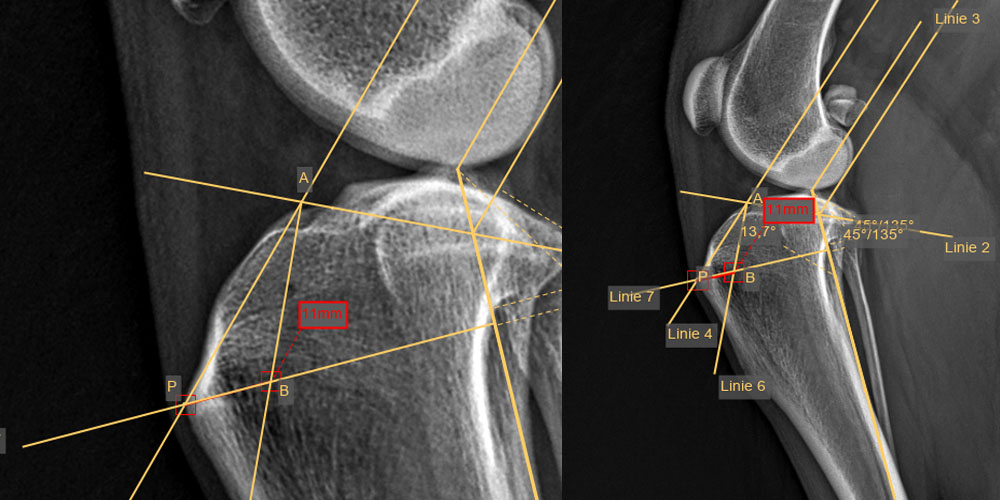

Kreuzbandriss — erkranktes Gelenk im Speziellen

Die häufigste Lahmheitsursache der Hintergliedmaße beim ausgewachsenen Hund und auch älteren Katzen ist ein Riss des vorderen Kreuzbandes, oft begleitet von einer Verletzung des inneren Meniskus. Kreuzbandrisse führen zu Instabilität, Meniskusfolgeschäden, Gelenksentzündung und Arthrosebildung im Kniegelenk. Bei einem Kreuzbandriss des Hundes liegt meist eine chronisch-degenerative Erkrankung zugrunde, weniger das scheinbar akute Trauma. Abhängig von Größe, Gewicht und Alter Ihres Tieres, sowie dem Verletzungs- und Arthrosegrad des Kniegelenkes empfehlen und führen wir die Meniskusdiagnostik und die für Ihr Tier angebrachteste Kreuzband-Operation durch. Die mit von uns weiterentwickelte, moderne TTA Rapid Methode zur Kreuzbandbehandlung mit dem Titan Implantat der Firma R.Leibinger medical bietet eine sehr frühe Wiederbelastung der operierten Gliedmaße und schnellere Genesung Ihres Hundes und Ihrer Katze.

- TTA Rapid® Tibial Tuberosity Advancement